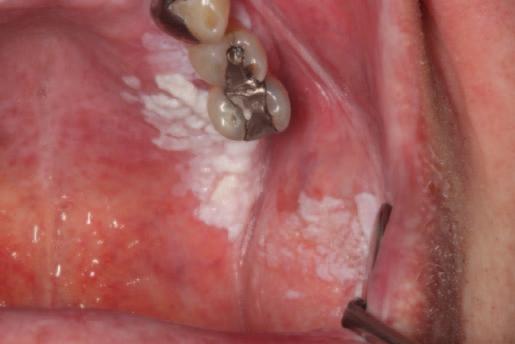

Daniel and Kayla are seven-year-old twins. They live with their parents in an estate in a large town. They are both outgoing and busy children. They enjoy school and activities with their friends. Daniel has mild autism. He has a special needs assistant in his classroom who helps him with his reading and language activities.

Daniel and Kayla have had uneventful visits to their family dentist once a year since infancy. Their teeth are brushed twice daily by their father. It is more challenging for Daniel as he does not always cope well with the flavour of the toothpaste. Recently, Daniel has found it more difficult due to sensitivity. Their dentist advised that Daniel has molar incisor hypomineralisation (MIH) and there was enamel breakdown on his newly erupted lower first permanent molars. Kayla’s teeth appeared normal. Bitewing radiographs showed that Kayla’s teeth were intact, but there were uncavitated lesions evident on Daniel’s primary molars.

Total 6; High*

*Even though the numerical score is 2, Daniel has a high risk of developing caries when considering the overall caries balance. This is due to the presence of MIH and the sensory challenges experienced in this case due to autism.

Actions:

Communicate risk to Daniel’s parents. Provide information regarding MIH. Advise continuing to brush Daniel’s teeth twice daily. Suggest unflavoured F toothpaste, e.g., Oranurse. Consider diet diary to provide tailored dietary advice. Plan and agree acclimatisation and preparation for Daniel’s future visits.

Apply topical fluoride varnish to at-risk sites; fissure seal uncavitated permanent molars. Consider glass ionomer sealant if isolation compromised or hypomineralised enamel present.

Stabilise molars with breakdown, e.g., using highviscosity glass ionomer cement, and set recall interval at three months. Further planning required regarding definitive management of first permanent molars.